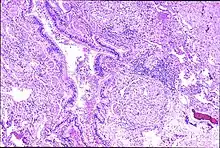

| Peribronchal non-necrotizing granuloma from berylliosis | |

Granulomas are seen in other chronic diseases, such as tuberculosis and sarcoidosis, and it can occasionally be hard to distinguish berylliosis from these disorders. However, granulomas of chronic beryllium disease will typically be non-caseating, i.e. not characterized by necrosis and therefore not exhibiting a cheese-like appearance grossly.[5]